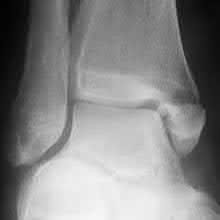

Figures A through C are AP, oblique, and lateral radiographic views of a right ankle demonstrating displaced fractures of the lateral and posterior malleoli. Figure D is an axial CT scan of the right ankle following closed reduction and splint application.

Figures A and B are the Lateral and AP radiographs of a displaced talar neck fracture with tibiotalar dislocation. Figures C and D are the post-reduction sagittal foot CT cuts that reveal a displaced talar neck fracture with medial

comminution.